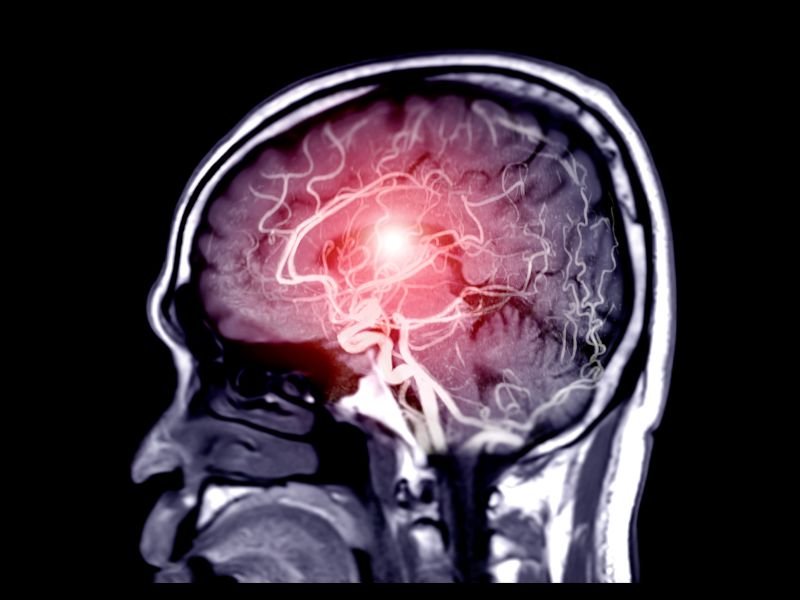

Os aneurismas cerebrais são dilatações anormais nas artérias do cérebro que, se não diagnosticadas e tratadas corretamente, podem levar a graves consequências para a saúde. Essa condição é considerada uma emergência médica, pois o rompimento de um aneurisma pode causar uma hemorragia cerebral, resultando em danos neurológicos permanentes ou até mesmo em morte. Neste texto, vamos explorar o que são os aneurismas cerebrais, seus sintomas, métodos de diagnóstico, opções de tratamento e a importância de contar com uma equipe médica altamente especializada.

Um aneurisma cerebral ocorre quando uma área enfraquecida de uma artéria no cérebro se expande ou se dilata, formando uma bolsa. Essa dilatação pode variar de tamanho e, quanto maior for o aneurisma, maior o risco de rompimento. O rompimento de um aneurisma é uma situação extremamente perigosa, pois provoca uma hemorragia subaracnoide, um tipo de sangramento que ocorre entre o cérebro e as membranas que o envolvem.

O diagnóstico de um aneurisma cerebral geralmente é realizado através de exames de imagem, como a tomografia computadorizada (TC), a ressonância magnética (RM) e a angiografia cerebral. Esses exames permitem que os médicos visualizem a estrutura das artérias cerebrais e identifiquem a presença de aneurismas.